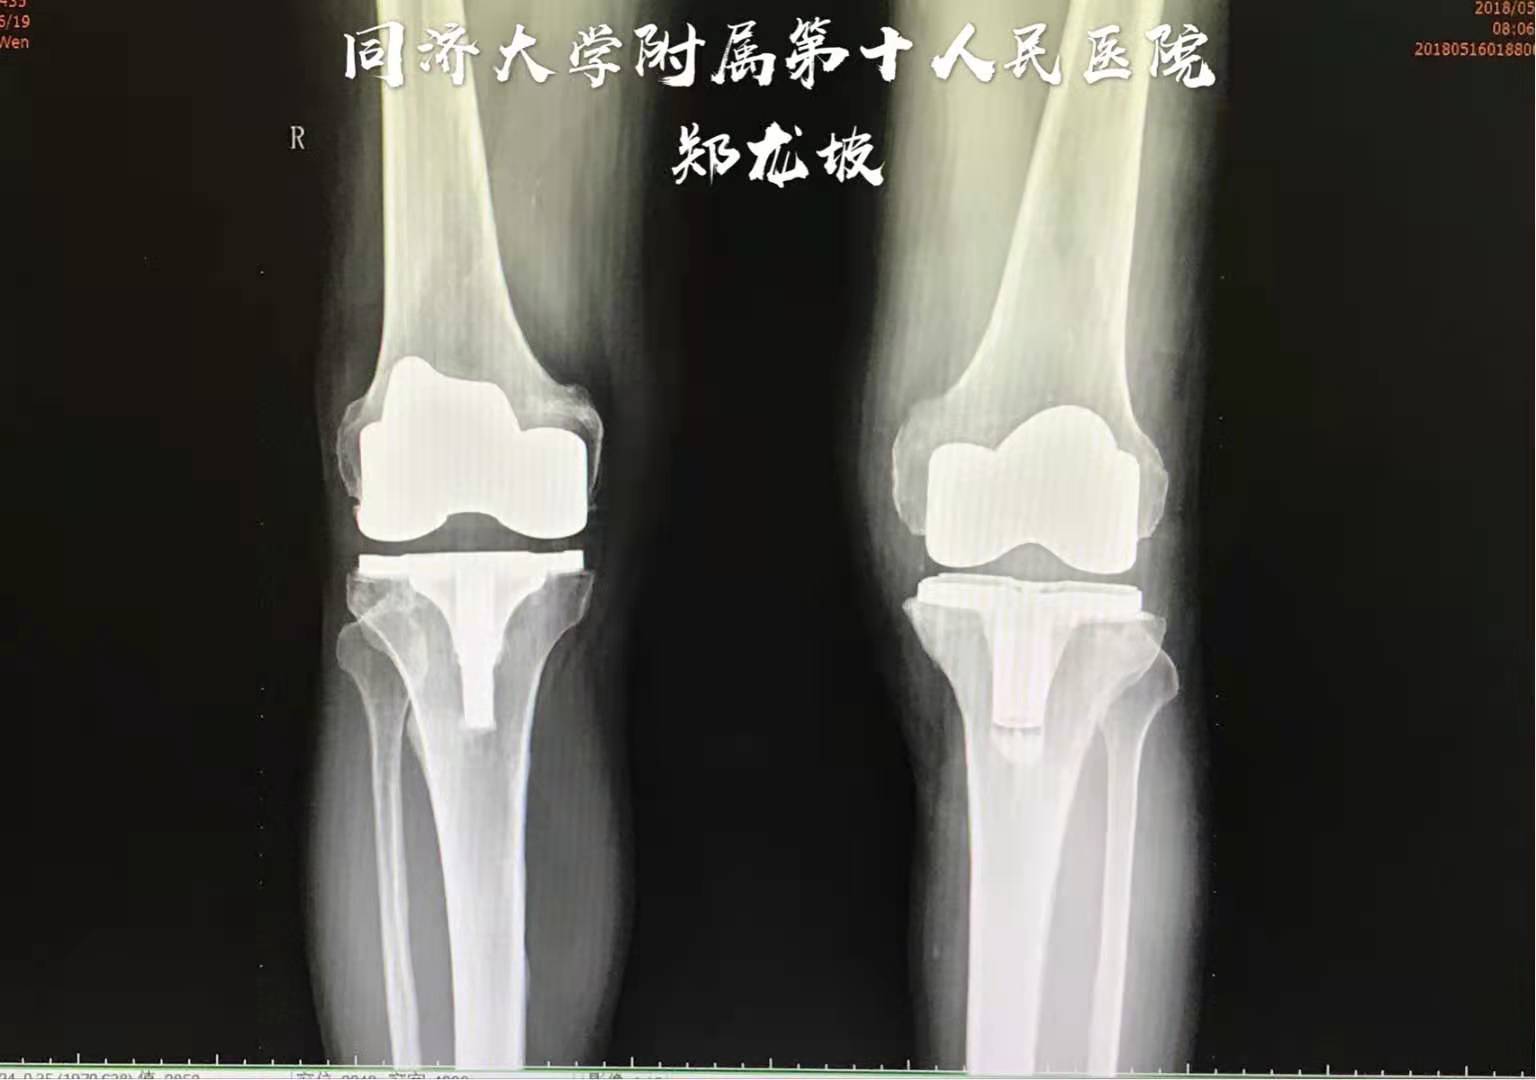

于2017年4月前先行症状较重的右侧膝关节表面置换

于2018年5月再行左侧膝关节表面置换

术后双下肢力线得到矫正